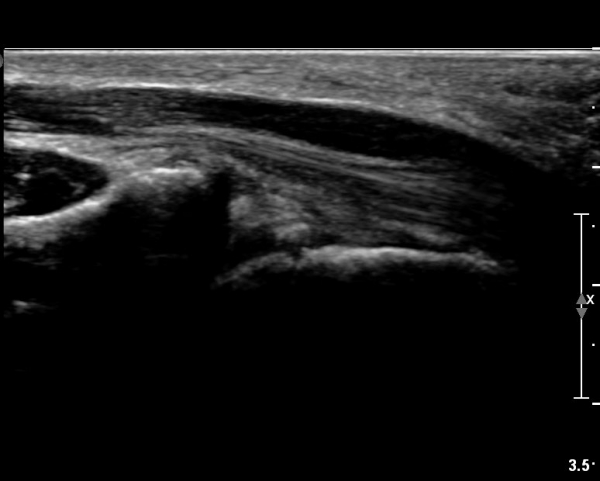

Á¤Á߽Űæ Á¾´Ü¸é°Ë»ç¿¡¼­µµ ¼Õ¸ñ ¸»´ÜºÎ¿¡¼­ ¼ö±Ù°ü ±ÙÀ§ºÎ±îÁö À̾îÁø Àú¿¡ÄÚ

Á¾¾çÀÌ °üÂûµÊ(»çÁø 8, 9, 10, 11).

µÎµ¢±ÙÀ°À» Áö¹èÇÏ´Â ¸»´Ü Á¤Áß½Å°æ °¡Áö º´Áõ ¼Ò°ßÀ» º¸¿© ÀÓ»óÀûÀ¸·Î ¼öÀåºÎ¿¡¼­

Á¾¾ç¿¡ ÀÇÇÑ Á¤Á߽Ű渻´Ü°¡ÁöÀÇ ¾Ð¹ÚÀÌ ÃßÁ¤µÇ¾úÀ¸³ª  ÃÊÀ½ÆÄ°Ë»ç»ó ¼Õ¸ñºÎÀ§¿¡¼­ Á¤Á߽Ű泻

Àú¿¡ÄÚ Á¾¾çÀÌ °üÂûµÇ°í Àú¿¡ÄÚ Á¾¾çÀÇ ½Å°æ³» À§Ä¡°¡ Âü°í¹®Çå¿¡¼­ º¸°íÇÑ ¹Ù¿Í °°ÀÌ

Á¤Á߽Ű泻¿¡¼­ µÎµ¢±ÙÀ°À» Áö¹èÇÏ´Â ¿îµ¿½Å°æÀÇ À§Ä¡¿Í ÀÏÄ¡ÇÏ¿© Á¤Á߽ŰæÁß¿¡¼­ µÎµ¢±ÙÀ°À»

Áö¹èÇÏ´Â ½Å°æ µ¢¾î¸®(fascicle)ÀÇ ½Å°æÁ¾À¸·Î ÃßÁ¤ÀÌ °¡´ÉÇϸç ÀÓ»óÀû ¼Ò°ß°úµµ ÀÏÄ¡ÇÑ´Ù.